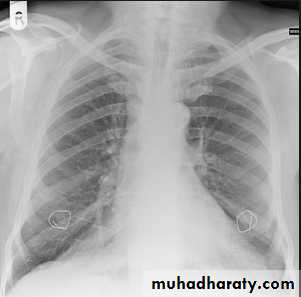

Nipples are usually in 5th ant. Rib space.

Nipple shadow